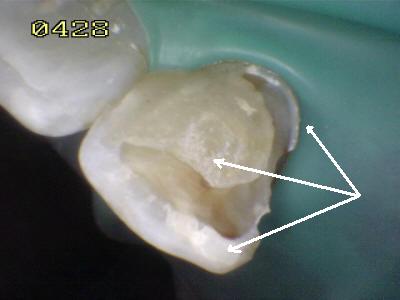

Puente Maryland con 20 años de servicio que se ha despegado por caries en la interfase diente cemento de resina.

Aspecto del puente tras 20 años de servicio  (Póntico con frente estético en resina Biolon)

Cemento de resina  adherido al metal

Cemento de resina  adherido al metal. Se ha utilizado el grabado electrolítico en acido sulfúrico, por ello se observa la tenáz adhesión al metal